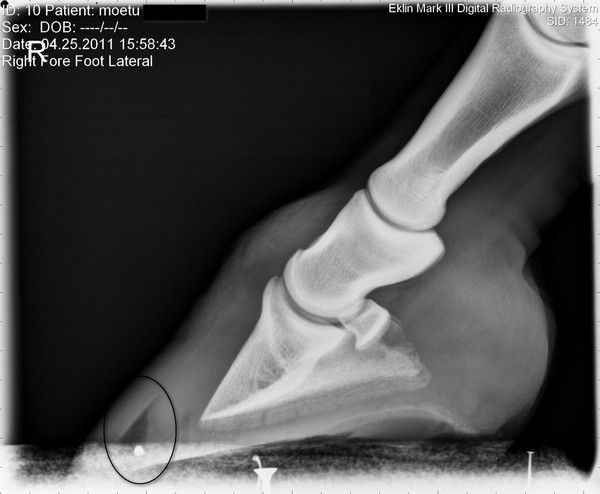

| Dire merci | Moi elle a des chaussons avec semelles amortissantes et soutien de fourchette et cela lui va très bien quand les parcs ne sont pas trop durs - exemple hier soir elle trottait allègrement je l'ai déjà vu faire quelques foulées de galop ...Par contre pied nu c'est l'horreur, même sur la dalle en béton. Et le matin au sortir du box, elle est toute raide, malgré la visite ostéo . J'ai essayé de la sortir en main mais on voit que c'est laborieux pour elle Concernant les soins, elle n'a rien ; le véto m'a dit : ce qu'elle a c'est comme si l'humain avait un ongle décollé, il faut attendre qu'il repousse et se recolle correctement ... mais il n'y a pas de soins particuliers à faire, car pas d'infection ni de pourriture, juste une nécrose des tissus ( qui sont d'ailleurs bien secs car je peux passer la brosse métallique sans souci) Le pb, si je peux dire, c'est que son pied pousse en talon et pas en pince - vu qu'elle pose le talon pour se soulager - et donc cela n'arrive pas vraiment à descendre alors qu'il faut parer le talon toutes les semaines ![]() ttr0pchoutoi Je vais voir pour la Cornucrescine mais est-ce qu'on peut n'en mettre que vers la pince ? Lokkur je vais regarder le iodamine équin aussi. Voici la radio de son antérieur avec la nécrose ![]() |

| Dire merci | El Bimbo en réalité la pince n'est pas trop longue, c'est l'angle de la radio qui est trompeuse ![]() De plus le véto m' a expliqué que c'était en forme de croissant, à savoir étroitement vers le bas puis plus large puis plus étroit en remontant vers la couronne - d'ailleurs on mesure l'écartement pour voir si ça descend bien - au départ c'était à peine visible et là on en est à 16 mm d'écartement ... Le véto a bien précisé qu'il ne fallait absolument pas toucher devant la fourchette , juste baisser les talons pour éviter les pb de tendons et rééquilibrer l'appui... Message édité le 10/08/11 à 11:05 Message édité le 10/08/11 à 11:13 |

DéconnectéDire merci | Ecoute, El Bimbo a raison. Si la paroi est décollée il ne faut plus qu'elle soit en appui sinon elle va continuer de se décoller au fur et à mesure de la pousse. Et les vétos jouent sur les mots. Elle n'est pas en fourbure aigue mais en fourbure chronique, la phalange est basculée et comme on n'a pas aidé par un parage convenable - baisser les talons et roll important de la pince - à se que la phalange se 'raccorche bien' on entretient cette fourbure. le véto te dit que l'ongle se détache. Oui. Quand tu as un ongle qui se détache, tu le coupes court ou bien tu le laisse pousser aur isque de te l'accrocher qqpart et de l'arracher encore plus? Les talons qui poussent plus vite c'est TYPIQUE de la fourbure chronique!! la sole rétrécie vers la fourchette, je vois trés bien ce que tu veux dire, c'est à cause de la bascule. Si tu pares convenablement tu finiras par voir que cette fameuse fourchette va reculer. La preuve de la fourbure: regarde la pince depuis la couronne, on le voit même sur les radios. La direction de pousse juste en dessous de la couronne est différente - plus 'verticale' sur quelques centimètres, puis il y a évasement là où la bascule s'accentue. |

| Dire merci | dejavu la paroi ne s'arrache pas, elle n'est pas décollée ; ce que tu vois sur la radio ce n'est pas un trou mais du tissu mort, presque aussi dur que la sole -le cure-pied ne s'y enfonce pas et le maréchal doit prendre sa renette pour le dégager petit à petit comme il le fait avec la sole morte ... En fait, pour simplifier, c'est comme un "durillon" que ma jument a en pince... Je précise aussi que lorsque la radio a été faite, le cheval venait d'être déferrée, depuis elle a été parée Le roll en pince a été fait mais on ne peut pas faire plus car cela a affiné la paroi et si on râpe plus, c'est le "durillon" qui va être mise à nu et va venir en appui...J'essaierai de faire des photos - avant - et après la venue du maréchal courant semaine prochaine - Message édité le 12/08/11 à 08:37 |

| Dire merci | Ca y est j'ai retrouvé le nom que le véto a employé au départ : il avait parlé d'un kératome ! Mais concernant Moëtu, ce serait d'origine traumatique et comme il y a plusieurs formes, origines, il a appelé ça une nécrose, " un genre de fourmilière" Et quand il parle "d'ongle décollé" il parle de douleur pour donner un ordre de comparaison . . . Message édité le 12/08/11 à 10:30 Message édité le 12/08/11 à 10:31 |